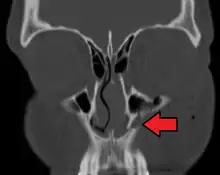

- the maxillary sinus

The maxillary sinus appears as a shallow groove on the nasal surface of the bone about the fourth month of development, but does not reach its full size until after the second dentition.

The maxillary sinus presents the appearance of a furrow on the lateral wall of the nose. In the adult the vertical diameter is the greatest, owing to the development of the alveolar process and the increase in size of the sinus.

A maxilla fracture is a form of facial fracture. A maxilla fracture is often the result of facial trauma such as violence, falls or automobile accidents. Maxilla fractures are classified according to the Le Fort classification.